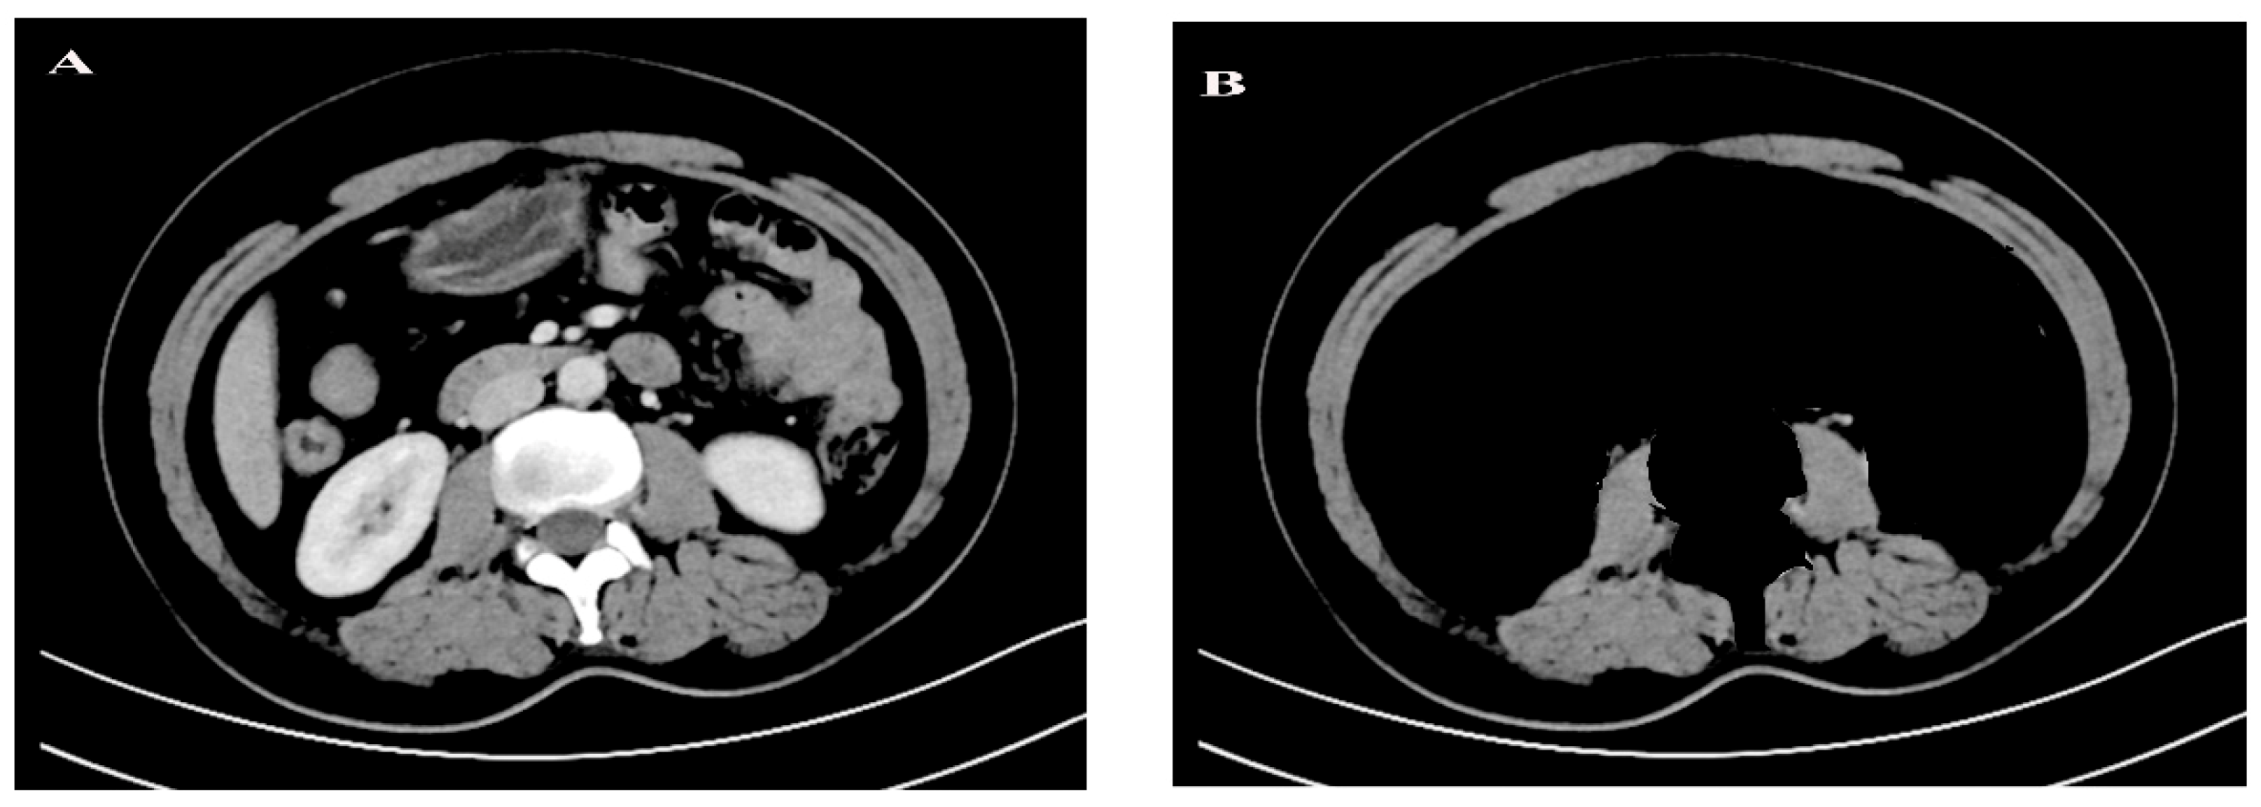

2.3. CT-Based Body Composition Analysis